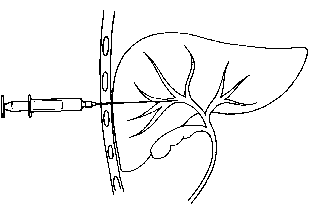

- Cholangiographie

transhepatique per cutanee : La cholagiographie

trans-hepatique est une radiographie des voies biliaires en

injectant directement dans le voie biliaire un produit de

contrast radio-opaque . Cela est possible nul que si elles

sont dilatees . La technique soit realise par une perfusion et

une injecte de calmant ,et anesthesie locale .Voie

d'abord est sur la ligne axilaire mediane ,au dessous de cul-de

sac pleural et dirige en direction vers le col de la 11e

cote . , on injecte le produit de contrast hydrosoluble et

prend les cliches imediatements . On peut utilisee le guide

de aiguille pour instalee une petite catheter pour drainage

la bile qui est en bloquee par un obstacle

. Technique se donne des images tres net des voies

biliaires intrahepatique i

Par une aiguille avec catheter place

a une des branche de voie biliaire le produit de

contrast a injecte suffisament pour opacifie

de tous le voie biliaire |

|

Voie d'abord est sur la ligne axilaire ,

au desous de cul de sac pleurale , dirrige vers le

col de la 11eme cote droit |